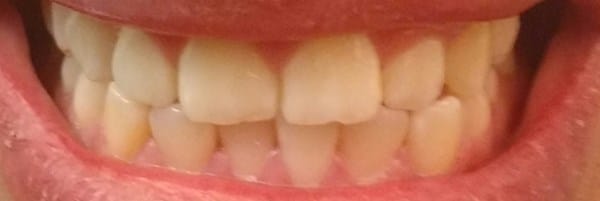

Tengo un dilema sobre que hacer en este momento. Tengo una muela con conducto partida la #27 y esta requiere una corona. Sin embargo, cuando me hice revisar me dijeron que era necesario que pensara en usar una corona temporal y realizarme una ortodoncia pues tengo un diente con mordida cruzada, la linea media un poco desviada y esto podría desgastarme los dientes. Mis dudas serían ¿en realidad necesito una ortodoncia o no es tan necesario y puedo dejar mis dientes como están? ¿Realmente puedo presentar problemas a futuro si decido no realizarme la ortodoncia? De antemano muchas gracias.

Adjunto fotos y una radiografía panorámica.